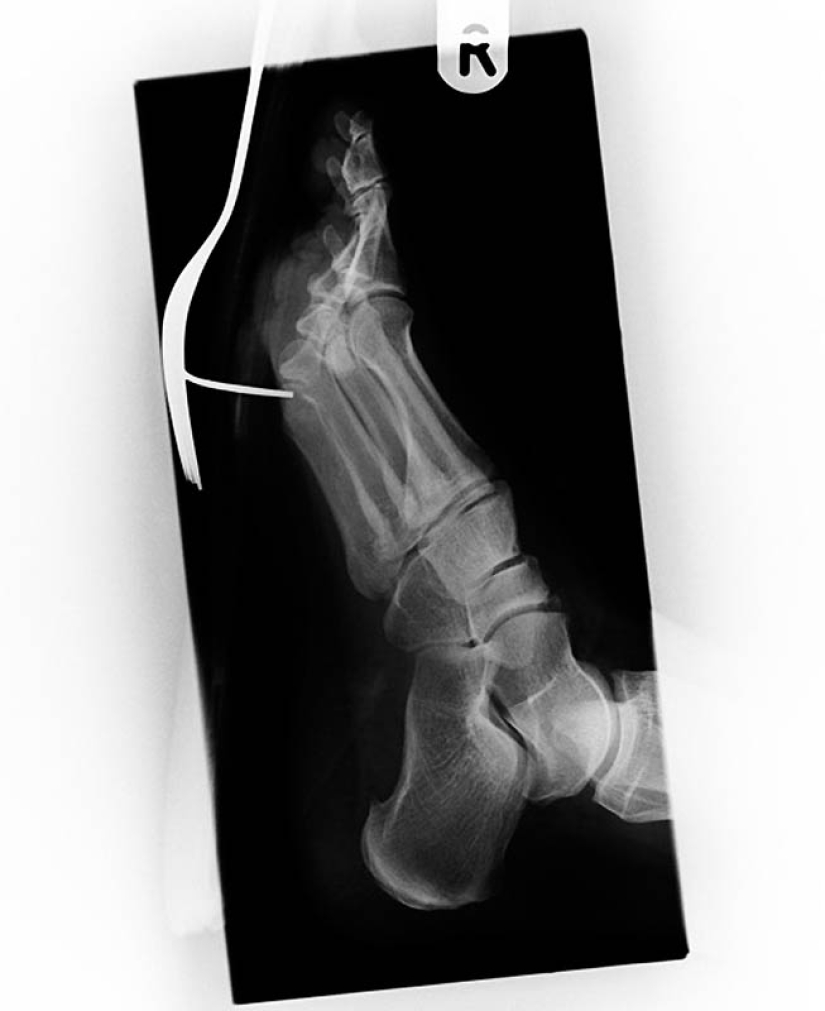

3. Ancient X-ray image of the foot of a soldier of the Anglo-Boer War (1899-1902) with a gunshot wound. The bullet lodged in the metatarsal bone between the thumb and second finger.